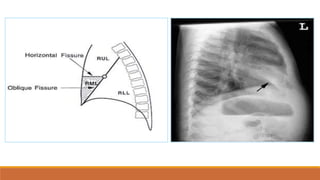

Các thùy phổi

- Phổi (P): Thùy trên, giữa và dưới

- Phổi (T): thùy trên và dưới